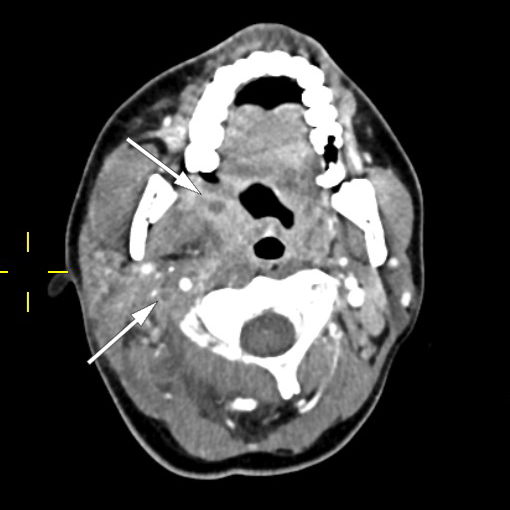

Pasienten ble videre undersøkt av vakthavende øre-nese-hals-lege. Man mistenkte abscedering, men trismus og smerter gjorde at det var vanskelig å få gjennomført en fullgod halsundersøkelse. Det ble derfor rekvirert CT collum. CT-funnene var forenlig med tonsillær/peritonsillær abscess bilateralt samt høyresidig trombosert vena jugularis med ledsagende tromboflebitt og flegmonøs betennelse (figur 1). På bakgrunn av dette ble Lemierres syndrom mistenkt. Abscessene ble vurdert som ikke modne for drenering, og det ble anbefalt bytte av antibiotika til klindamycin intravenøst, 600 mg × 3, hvilket ble startet opp neste dag. Grunnet trombosetendensen ble det også forordnet lavmolekylært heparin (enoksaparin), dosering 60 mg subkutant morgen og 40 mg subkutant kveld. P-piller (etinyløstradiol) ble seponert, da disse kan gi økt trombosetendens.

Pasienten fikk smerter i venstre del av toraks på dag 2. CT toraks og abdomen viste funn forenlig med septiske embolier i begge lunger og mulig infarktkomponent i høyre underlapp (figur 2, figur 3). I tillegg var det lett forstørret lever og milt, periportalt ødem samt små mengder fri væske i bekkenet (mulig fysiologisk). Det var også beskrevet mistanke om tromber i vena subclavia og vena axillaris på høyre side. Dag 3 så man oppvekst av penicillinfølsomme Streptococcus anginosus i blodkultur. Serologiske prøver viste svakt positivt Epstein-Barr-virus (EBV)-viralt kapsidantigen (VCA)-IgG, svakt positivt EBV-VCA-IgM og negativt EBV-EBNA-IgG. Intravenøst benzylpenicillin og klindamycin samt antikoagulasjonsbehandling med lavmolekylært heparin (enoksaparin) ble kontinuert.